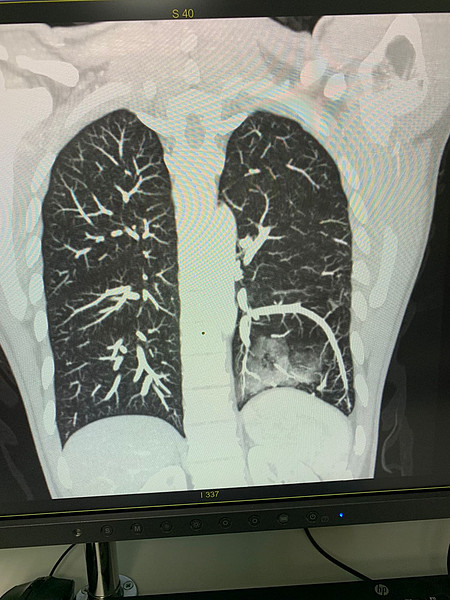

IMG-20211226-WA0002.